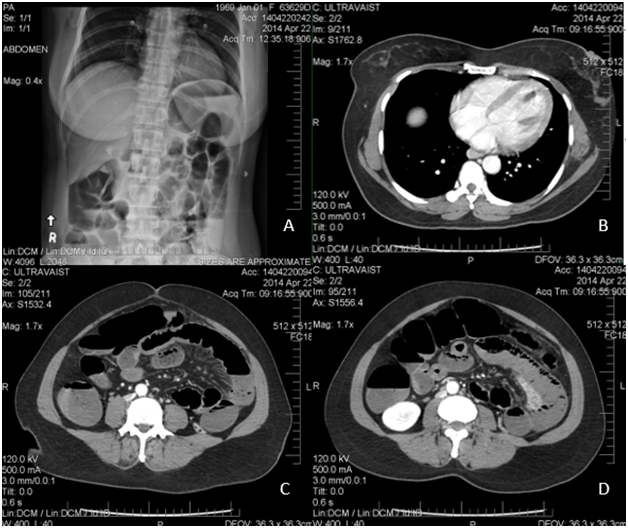

The patient also underwent numerous radiological studies, an abdominal x-ray showed dilated bowel loops. An emergent CT scan of the abdomen that confirmed a small intestinal ischemia with a superior mesenteric thrombus (Figure 1). Due to this, an echocardiogram was performed which showed a severe global hypokinesia of the antero-lateral left ventricle with a mobile thrombus attached to the akinetic portion of the apex with an ejection fraction of 25 % (Figure 2).

Figure 1 Dilated small bowel segments with edematous and thick-walled jejunal loops and multiple air-fluid levels due to a superior mesenteric thrombus associated with a left ventricle filling defect. Abdominal X-Ray (A); CT Scan without contrast: Transverse Views (B, C, and D).